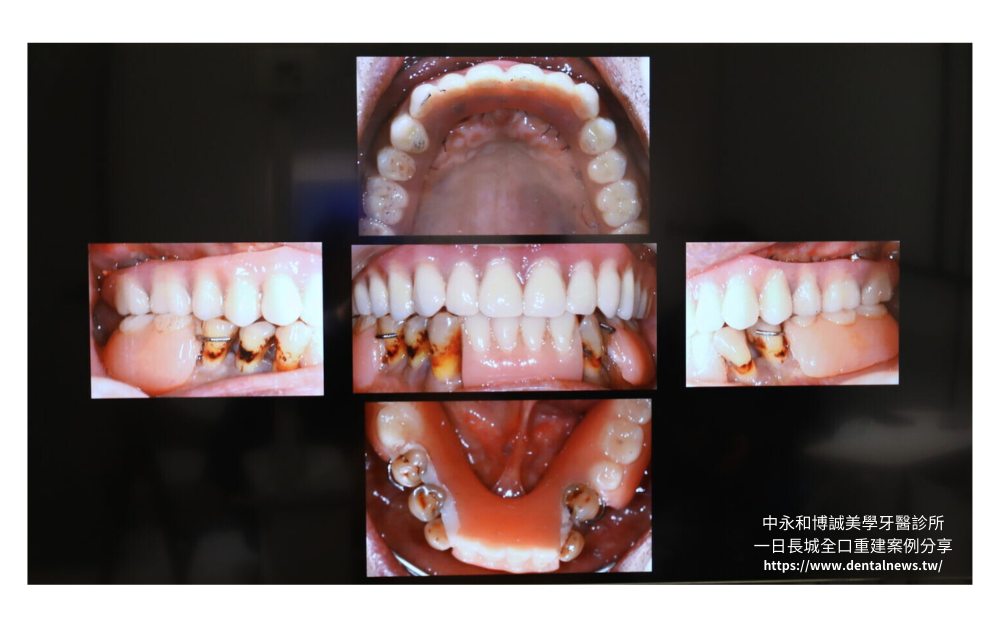

一日長城全口重建植牙術式介紹

除了上述提到的一般植牙、即拔即種的方式之外,還有今日的重頭戲「一日長城全口重建植牙」。

「一日長城全口重建植牙」厲害的地方在於能夠地將4~6個植體牢牢固定於齒槽骨中,植體可以互相提升整體的穩固感和穩定性,同時也確保植牙更能輕鬆應對咀嚼和其他口腔運動所帶來的各種壓力,植牙變得如此簡單,不再是煩惱!

一日長城的優點在於使用4~6根較短的植體,植入齒槽骨中,能夠提供較高安全性。在假牙支撐方面,一日長城使用鈦金屬銲接骨架,並提供客製化假牙製作服務,讓患者在咀嚼的時候能夠達到與真牙無異的效果。